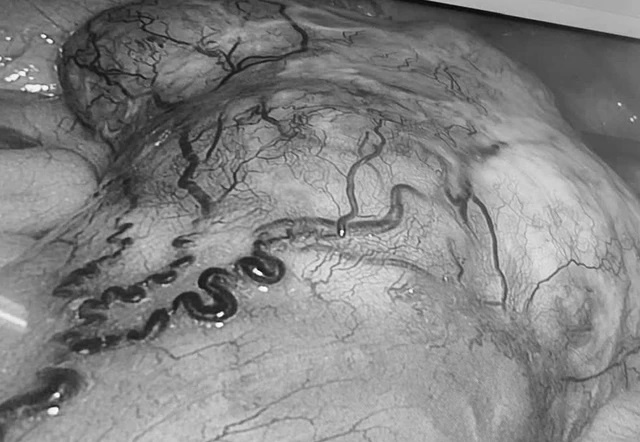

Hình ảnh U GIST qua màn hình nội soi. Ảnh: BVCC.

Tại khoa Ngoại Tổng quát, Bệnh viện Đa khoa Vĩnh Long, bệnh nhân được các bác sĩ khai thác bệnh sử chi tiết, thăm khám lâm sàng kỹ lưỡng, đồng thời chỉ định thực hiện các cận lâm sàng chuyên sâu: Nội soi đại tràng ghi nhận tổn thương u sùi, gây hẹp lòng đại tràng, hình ảnh nghi ngờ ác tính. Chụp CT-scan ổ bụng phát hiện thêm một khối u đặc vùng hạ vị kích thước khoảng 10 x 10 cm, xuất phát từ ruột non, hình ảnh gợi ý u mô đệm đường tiêu hóa (GIST).

Việc phát hiện đồng thời 2 khối u tại hai vị trí giải phẫu khác nhau, với bản chất bệnh lý hoàn toàn khác nhau, đã khiến ca bệnh trở nên đặc biệt phức tạp, đòi hỏi phải có chiến lược điều trị tối ưu và thận trọng ngay từ đầu.